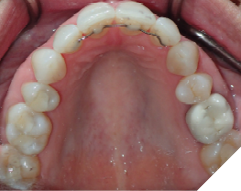

The majority of the orthodontic practices offer a period of “supervised retention” to their patients and communicates the customized retention recommendation with the patient’s general dentists. It is extremely important to work as a team to achieve long term clinical success in maintaining a functional bite and aesthetic smile. The general dentists continue to see their patients on a regular basis and have an opportunity to assess the orthodontic retainers and the bite after the supervised retention period is completed by the orthodontists. With great care, orthodontic retainers would serve for a long time (Fig. 1) without any major issues. However, in some cases, the failure to notice the clinical problems early on results in functional issues that would require a comprehensive orthodontic treatment to correct it (Fig. 2).

Fig. 1A

Fig. 1B

Fig. 1C